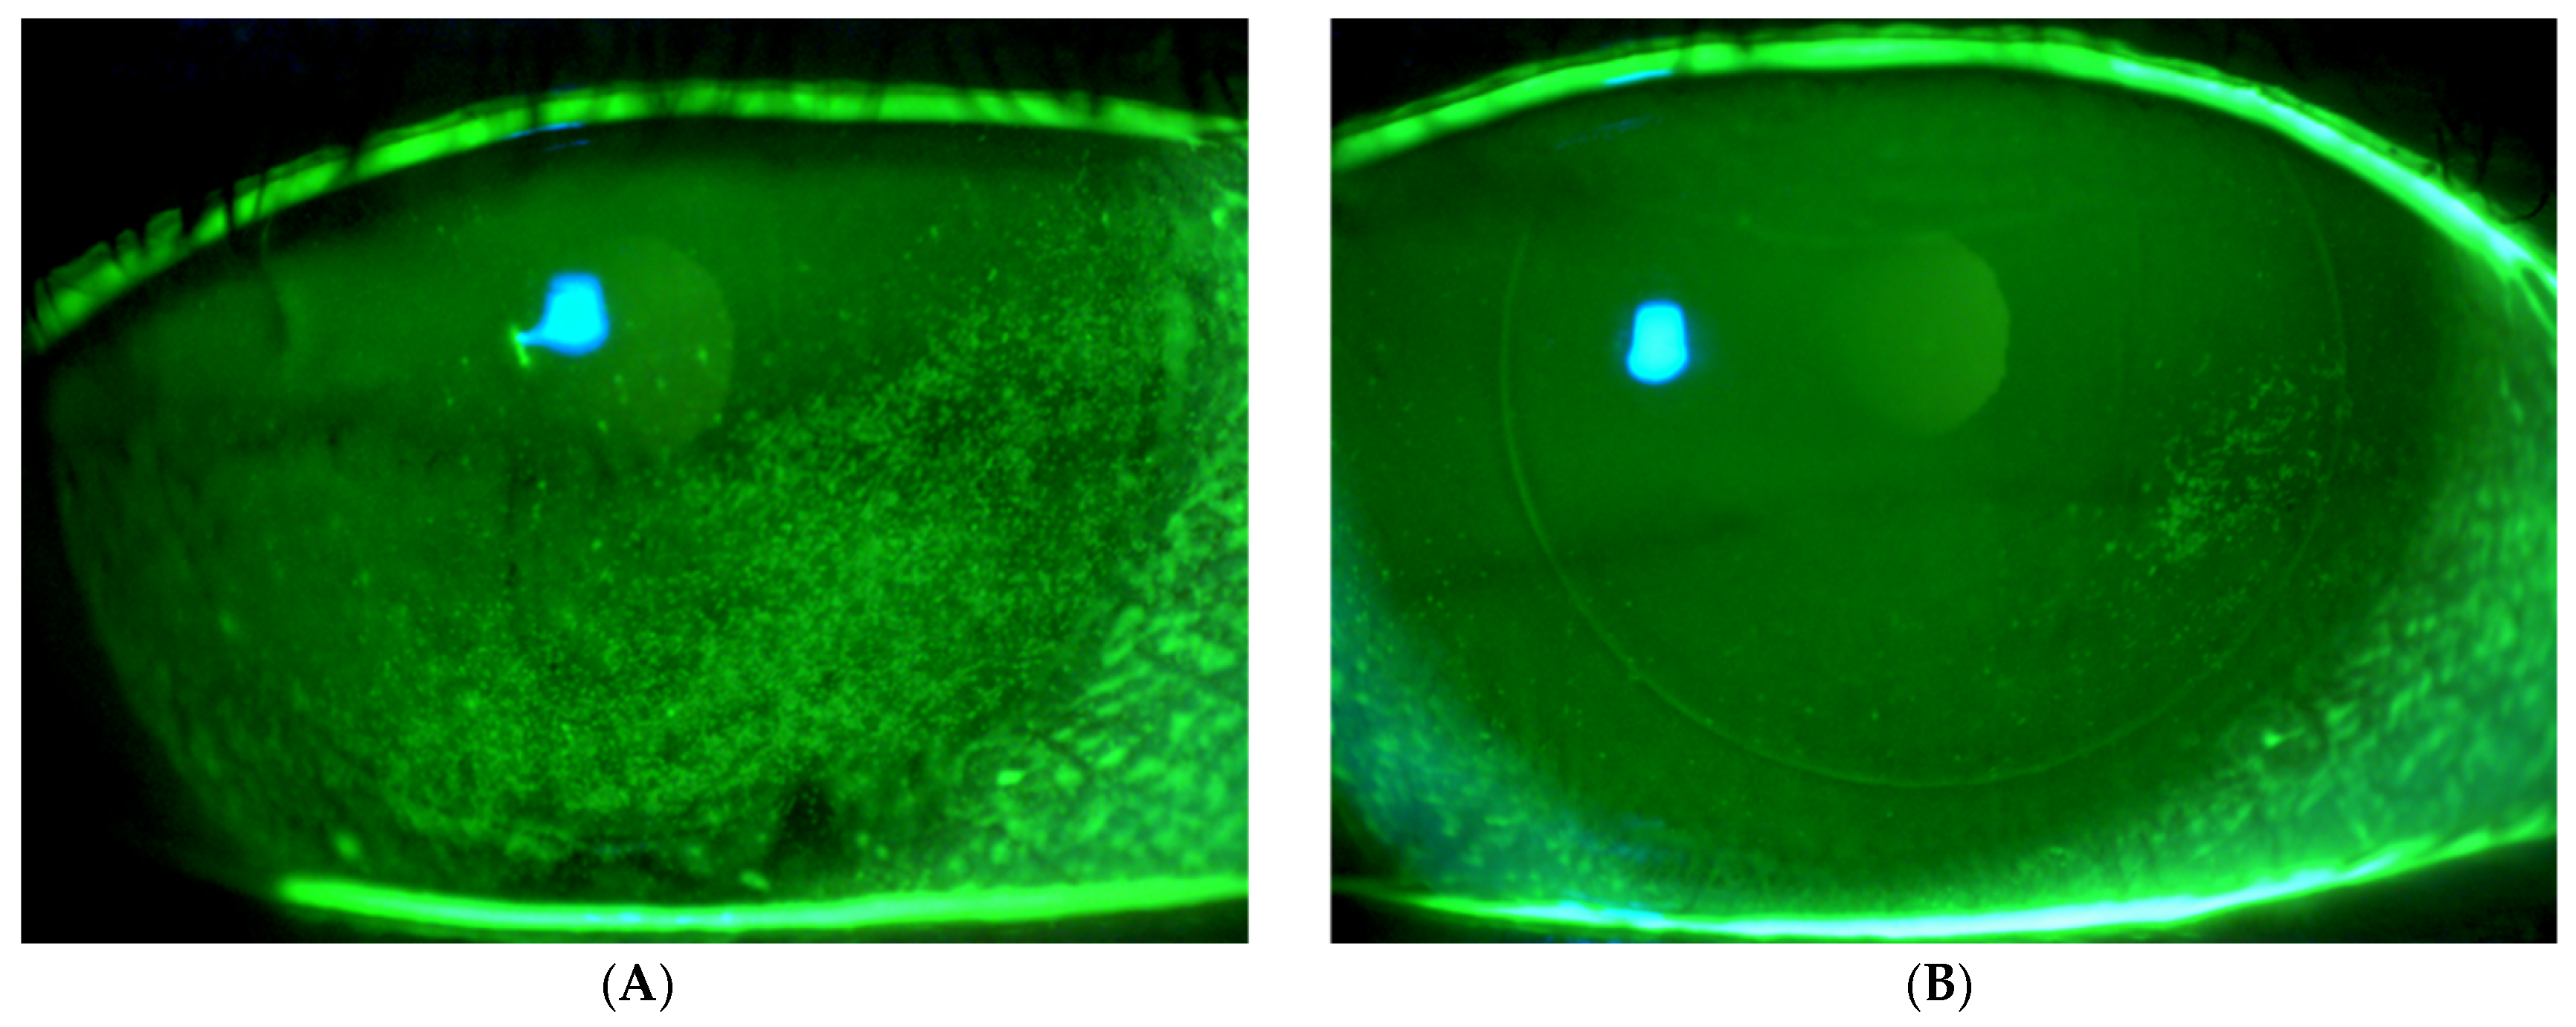

- Sher, I.; Tzameret, A.; Szalapak, A.M.; Carmeli, T.; Derazne, E.; Avni-Zauberman, N.; Marcovich, A.L.; Ben Simon, G.; Rotenstreich, Y. Multimodal Assessment of Corneal Erosions Using Optical Coherence Tomography and Automated Grading of Fluorescein Staining in a Rabbit Dry Eye Model. Transl. Vis. Sci. Technol. 2019, 8, 27. [Google Scholar] [CrossRef]

- Chun, Y.S.; Yoon, W.B.; Kim, K.G.; Park, I.K. Objective assessment of corneal staining using digital image analysis. Investig. Ophthalmol. Vis. Sci. 2014, 55, 7896–7903. [Google Scholar] [CrossRef] [PubMed]